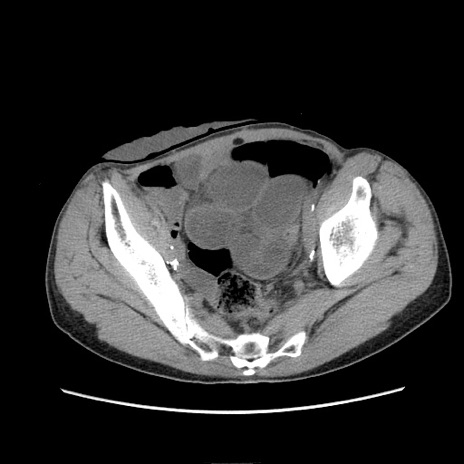

冠状断像

症例11(横断像)

【症例】 60歳代男性

【主訴】 下腹部痛

【現病歴】 本日夜中より下腹部痛の症状認め、受診。

【既往歴】 膀胱癌(膀胱全摘+尿管皮膚瘻術) 、胃癌術後

【身体所見】 BT 35.3℃、PR 58/min、BP 136/98mHg、腹部平坦、軟、腸蠕動音±、ストマ留置あり、左上腹部~正中部に圧痛あり、反跳痛なし。

【データ】WBC 5100、CRP0.01